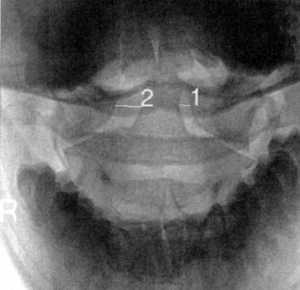

КТ и цифровая спондилография - важные методы диагностики вывихов атланта (рис.

1.7 и 1.8). МРТ позволяет определить не только дислокацию атланта, но и степень

Рис 1.7. Ротационный вывих атланта по

данным цифровой спондилографии |

|

Рис. 1.8. Вывих в атланто-аксиальном сочленении по данным

цифровой спондилографии |